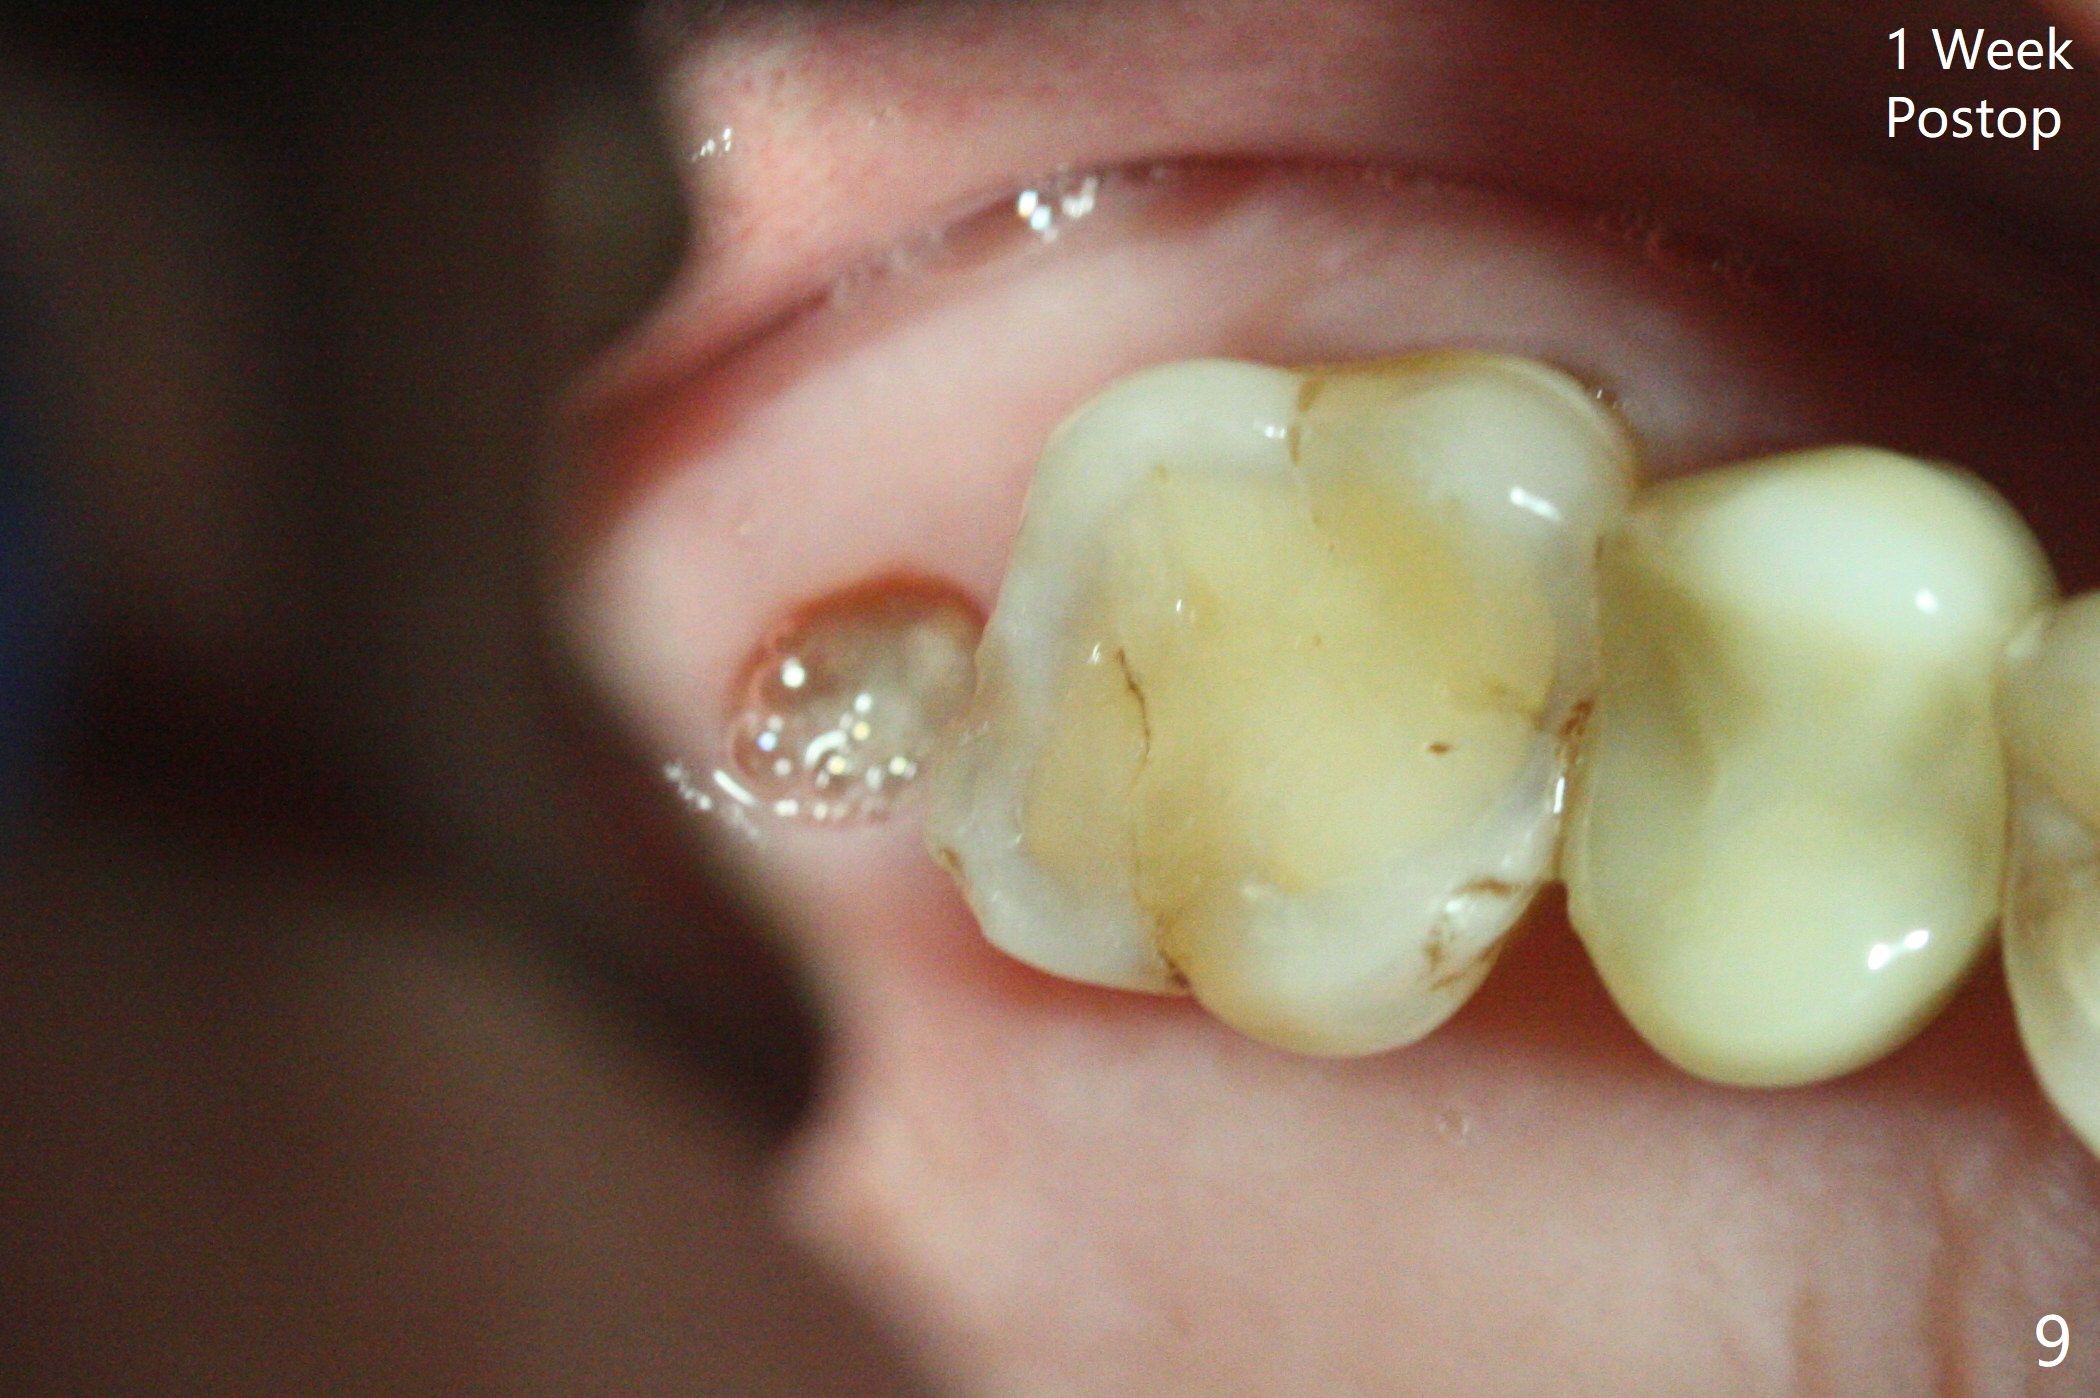

66岁男右上,左上7导板延期种植(足够角化龈,使用环形切刀),都提升,但是前者未植骨(图一,二(骨高度多,进入上颌窦少)),后者植骨(图六(*),七),由于扭力低(小于15Ncm),放置愈合螺帽和剪成圆形六个月胶原膜,使用牙周胶水(图三,八),之后不再放置牙周敷料。当钻头接近左侧上颌窦底板时,放置骨粉(图四-六:*),使用报废植体(图四,五)和正式植体(图六)将骨粉推入上颌窦。术后病人抱怨食物撞击伤口疼痛,即刻修复减少术后疼痛。术后5个月没有骨质吸收,基台完全就位(图十一,二)。